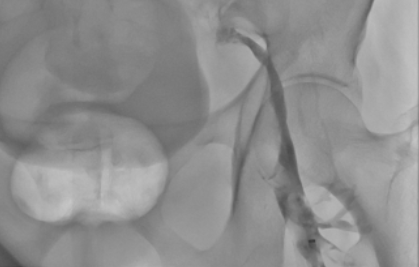

The patient, a 73-year-old female, developed swelling of the left lower limb 3 days before admission without any obvious precipitating factors. She also experienced soreness, fatigue, and coldness of the limb, but she did not pay attention to it and did not receive any diagnosis or treatment. Subsequently, the swelling of the left lower limb progressively worsened, and her movement was significantly limited. The color Doppler ultrasound of the lower extremity veins in an external hospital showed thrombosis in the left external iliac vein, common femoral vein, deep femoral vein (branch segment), upper and middle segments of the superficial femoral vein, and intermuscular veins. She was admitted to the Department of Cardiac Intervention on February 12, 2025, with the diagnoses of "1. Lower extremity venous thrombosis; 2. Iliac vein compression syndrome". After admission, "inferior vena cava filter implantation + lower extremity venous catheter thrombolysis" was performed. After the operation, "heparin sodium injection" was given for anticoagulation, and "urokinase for injection (400,000 units) was pumped intravenously twice a day" for thrombolysis. After thrombolytic treatment, the reexamination of the lower extremity venography showed that the thrombus burden was significantly reduced. Then, iliac vein stent implantation was performed. After the operation, rivaroxaban was continued for anticoagulation treatment.

Lower Extremity Venography Thrombus Aspirated during the Operation